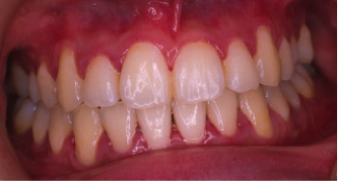

過蓋咬合(かがいこうごう)※ 非抜歯

20歳/女性

悩み:噛み合わせが深い

下の前歯が上の歯茎に食い込んでいる状態

治療期間:約2年

治療前

治療後

深い噛み合せを改善する治療が必要になりました。

先に深い噛み合せを上げないと矯正装置がつかないので、噛み合せの深さを改善する治療から行なう矯正治療となりました。